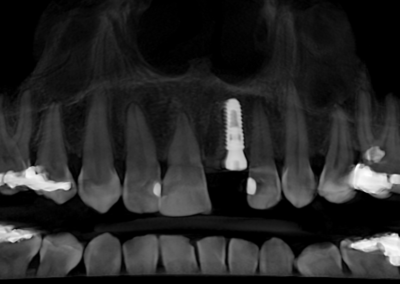

We start with a comprehensive full mouth examination, digital X-rays, a dental 3D(CBCT) scan and Trios5 Scan. The scanned images provide high-resolution images in a three dimensional plane. We use these images and scans for precise treatment planning.

CBCT 3D Scan

Using the 3D images in special planning software, the Dentist maps out the exact position and angle of insertion of each implant. They take care to place implants where they will be stable and in the best position to support the replacement teeth. They will also plan out any bone grafting (if needed) to ensure the implants have strong bone support.